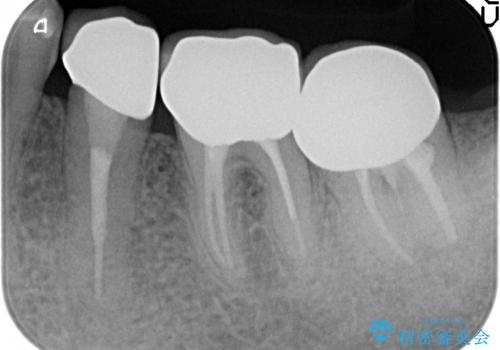

手術後歯茎の治癒を待ち、オールセラミッククラウンによる補綴を行いました。

今回用いたオールセラミッククラウンはジルコニアフレームという白い素材の上にセラミックを盛っているため、審美性が非常に高いのが特徴です。

また、ジルコニアは人工ダイヤモンドの材料にも使われているほど高い強度を持っており、そのためオールセラミッククラウンは審美性だけでなく、奥歯やブリッジの補綴も可能とするクラウンです。